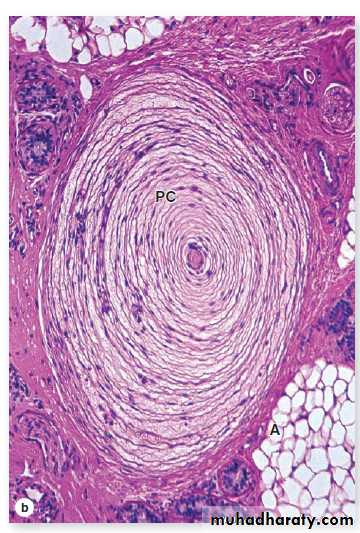

Lamellated (pacinian) corpuscles (PC) detect coarse touch or pressure and are large oval structures, frequently 1 mm in length, found among adipose tissue (A) deep in the reticular dermis or in the subcutaneous tissue. Here the outer connective tissue capsule surrounds 15-50 thin, concentric layers of modified Schwann cells, each separated by slightly viscous interstitial fluid. Several axons enter one end of the corpuscle and lie in the cylindrical, inner core of the structure. Movement or pressure of this corpuscle from any direction displaces the inner core, leading to a nerve impulse. X40. H&E.